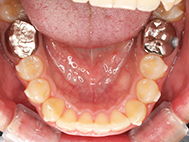

Before

| 症状 | 上顎前歯部叢生 |

上の前歯がハの字隣の歯が引っ込んでいる

前歯のガタガタが気になるとの事で来院されました。

装着が目立ちたくないとの事でアライナ-での矯正を希望されました、歯の間を削り少し歯の幅をスリムにして綺麗なアーチに並びました。